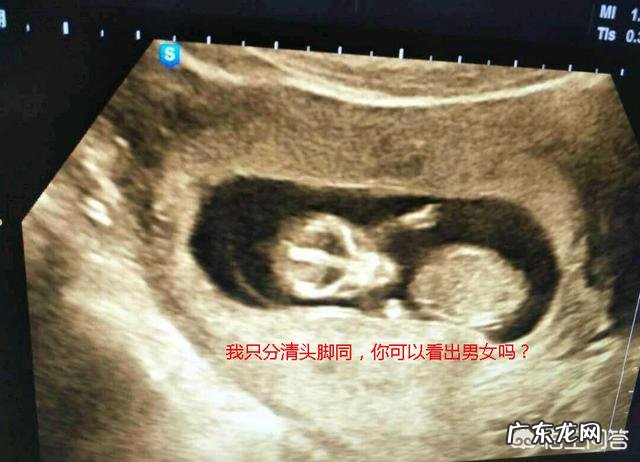

怀孕十二周时胎儿的性别不是就已经形而外了 , 不但是基因那XX还是XY的区别了 , 这时候一般外生殖器就已经开始显现了 , 而用B超也可以看出来了.

但是非常遗憾 , 现在国家明文规定 , 没医学的指征 , 不要用B超照男女.

所以孩子的生殖器是生出来了,但是只有B超医生看得到,不能告诉你了.